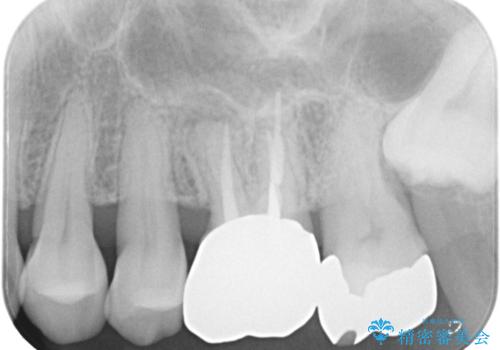

【根管治療】ズーンと痛い歯の治療。

- 奥歯付近がジーンと痛いことを主訴に来院されました。

左上7番の歯は、歯髄検査にて反応を示し、歯周ポケットはありませんでした。

親知らず抜歯を行い、痛みの変化や歯根吸収の有無を確認したのち、抜髄処置を行っています。

症状改善し、遠心の骨の回復も認めます。

バイオセラミックシーラーを使用して根管充填を行っています。